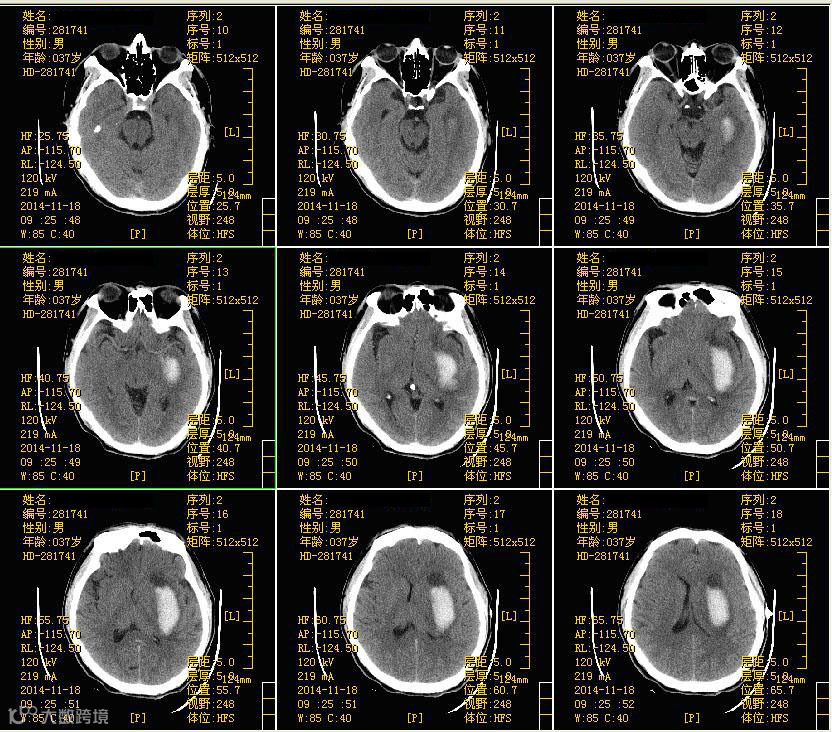

颅脑CT检查:左侧基底节区脑出血并血肿形成。

术前脑部CT图